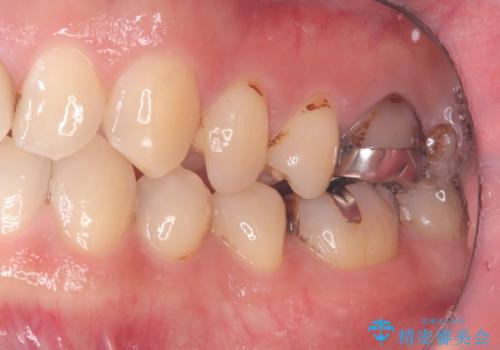

- CRが劣化し欠けてしまっている状態でした。 虫歯を除去後、歯を破折から守るためオールセラミッククラウンで治療を行いました。

CRが欠けてしまっていて食べ物が凄く詰まる状態でした。